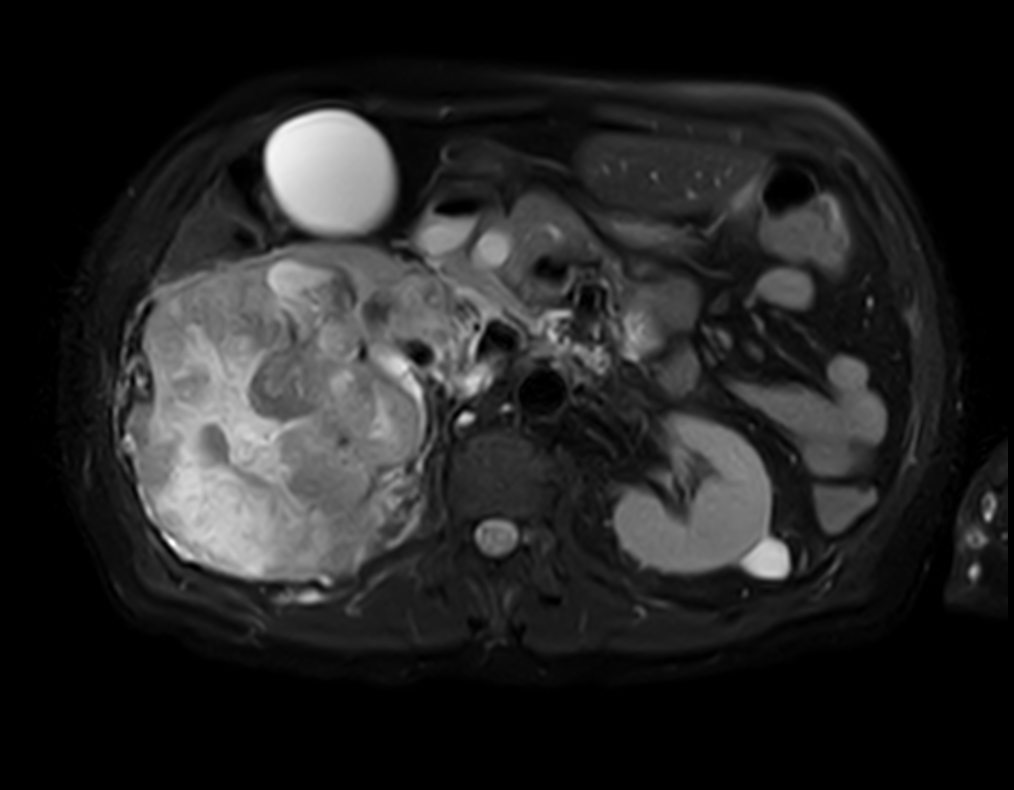

Patient with kidney tumor. ExamCard includes Compressed SENSE to shorten the breath hold time, VitalEye for touchless respiratory sensing, mDIXON XD FFE to acquire up to four image types in one single scan, DWIBS to achieve high contrast between background and lesions and bTRANCE for non-contrast time-resolved imaging.

T2w SPAIR - VitalEye Compressed SENSE